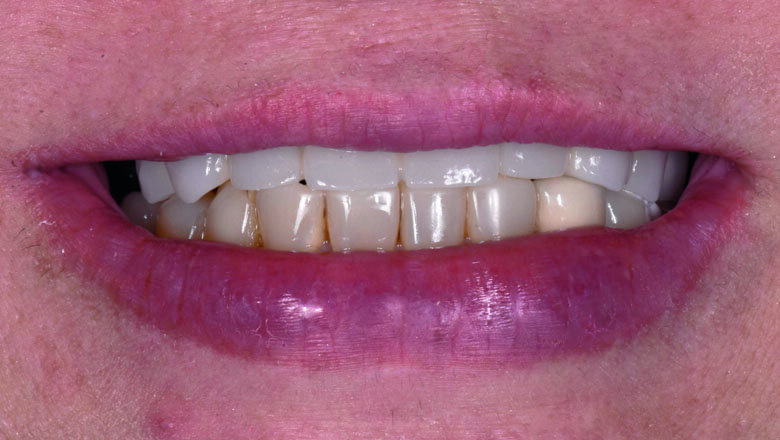

The initial clinical examination revealed a long-span Porcelain-Fused-to-Metal (PFM) FDPs of teeth 14-25 fixed with temporary cement since 2009 at private hospital (Fig 1,2). The patient had maxillary hard and soft tissue defects associated with alveolar ridge resorption and loss of lip support. Removable Acrylic Gingival Veneer (AGV, Fig 3.) was used to cover those FDPs in order to improve extra-oral soft tissue profile (Fig 4.). Without AGV, the patient has concave profile (Fig 5.). FDPs were removed to evaluate the existing abutments condition (Fig 6.). Abutment teeth 13,24,25 had first degree mobility. Panoramic XRAY (Fig 7.) revealed that tooth 13 had cast post and core with vertical root fracture. Tooth 25 was endodontically treated with a periapical lesion. After thorough diagnosis and analysis, the treatment plan was presented to the patient with the following phased treatment approach:

3) Flapless guided-surgery with immediate loading protocol

Fig 4. Extraoral smile with FDP in place

Fig 21. Fully-guided surgery was performed using Nobel Active

Fig 22. Post-operative panoramic XRAY

Fig 23. Post-operative occlusal view

Fig. 24. Post-operative frontal view

Fig 25. Post-operative smile with provisional profile prosthesis

Fig . 26. Post-operative smile with provisional profile prosthesis

Fig 27. Post-operative smile with provisional profile prosthesis

The existing provisional bridge was utilized for converting to a provisional screw-retained prosthesis. An immediate loading protocol was utilised2. Metal temporary abutments were connected on each implant. Provisional full arch bridge was perforated to match the position of the metal temporary abutments, placed in their correct position and OVD, relined with self-cure acrylic resin. All surfaces were fine-polished. A light-cure denture sealant (Palaseal, Kulzer) was applied on the intaglio surface. The provisional bridge was delivered to the patient’s mouth. (Figs. 23-27) Post-operative panoramic XRAY revealed that implants were placed according to the pre-operative planning (Fig. 22) Suture was removed after surgery 14 days. A final profile protheses3 will be fabricated after implant osseointegration.